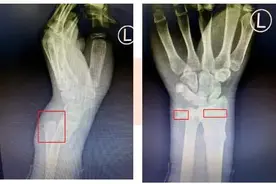

4月28日,新疆阿勒泰地区第二高级中学的高三学生阿曼卓力·阿依恒,在新疆师范大学参加体育加试800米项目时,因旧伤复发和跟腱撕裂,摔倒在距离终点不到30米处,最终阿曼卓力·阿依恒凭借坚定意志,忍痛爬到终点,完成比赛。